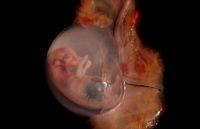

التعريف المقبول للإجهاض الطبيعي هو إسقاط الجنين، الذي يحدث قبل الأسبوع الـ 20 للحمل.

الإجهاض الفائت – هذا المصطلح يشير إلى الحمل الذي توقف عن التطور داخل الرحم لعدة أسابيع.